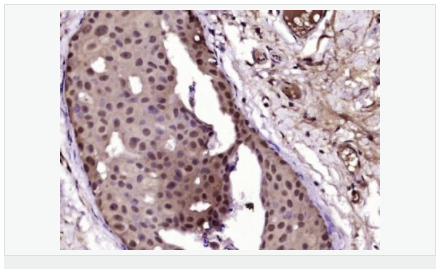

| 英文名稱 | Progesterone Receptor |

| 中文名稱 | 孕激素受體抗體 |

| 產(chǎn)品應用 | WB=1:500-2000 IHC-P=1:100-500 IHC-F=1:100-500 Flow-Cyt=1ug/Test ICC=1:100-500 IF=1:100-500 (石蠟切片需做抗原修復) not yet tested in other applications. optimal dilutions/concentrations should be determined by the end user. |

| 細胞定位 | 細胞核 細胞漿 |